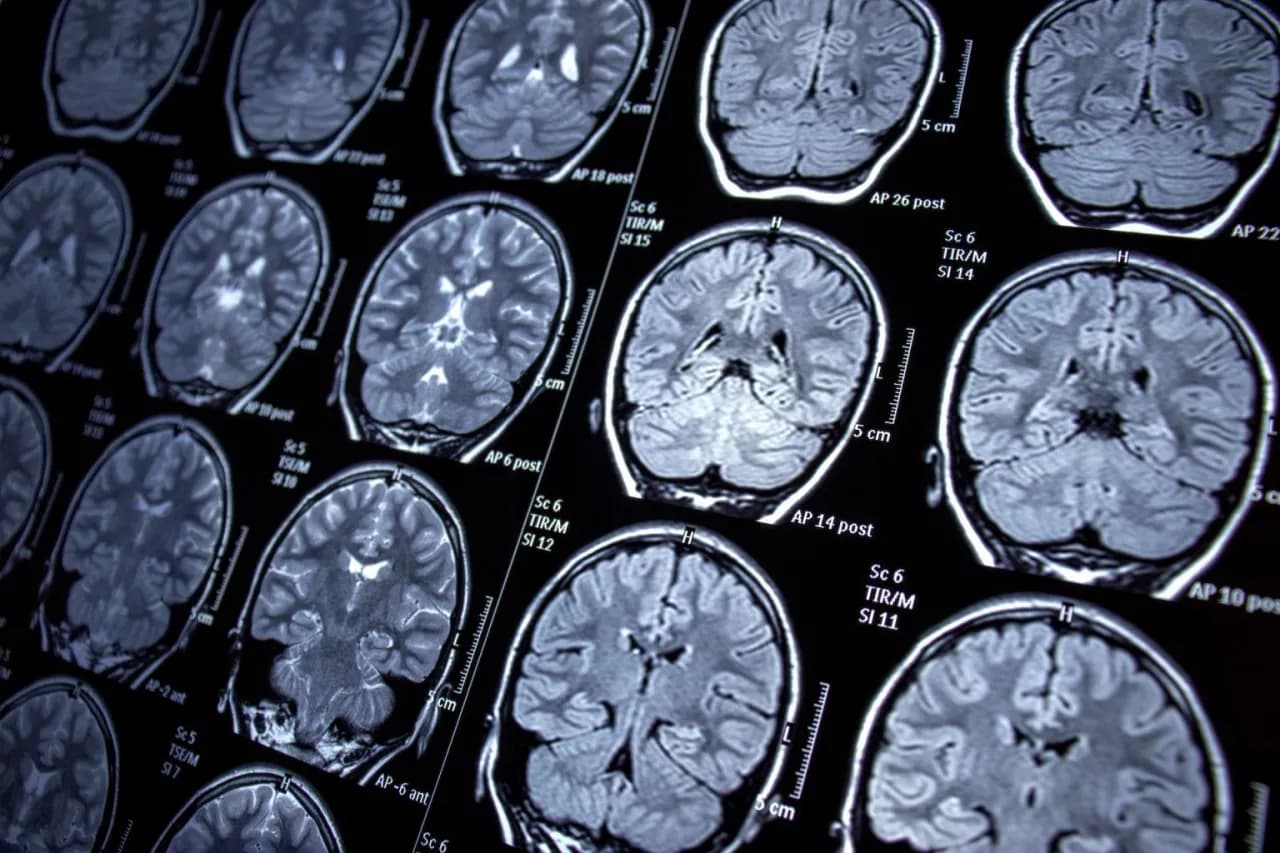

Rezonans magnetyczny (MRI) – obrazowanie strukturalne mózgu w diagnostyce

Rezonans magnetyczny (MRI) jest kluczowym badaniem w diagnostyce neurologicznej, które pozwala na uzyskanie szczegółowych obrazów struktur mózgu. Dzięki MRI lekarze mogą ocenić obecność zmian, takich jak guzy, urazy czy inne nieprawidłowości. Użycie tej metody jest nieocenione w przypadkach, gdy istnieje podejrzenie, że napady mają podłoże organiczne.- Wiek pacjenta

Tomografia komputerowa (CT) to kolejne istotne badanie, które jest często zalecane w diagnostyce padaczki, szczególnie gdy podejrzewa się urazy lub krwawienia w mózgu. Badanie to jest szybkie i skuteczne w wykrywaniu nieprawidłowości strukturalnych, które mogą prowadzić do napadów. Choć MRI jest bardziej dokładne, CT jest często stosowane w nagłych przypadkach ze względu na szybkość działania.